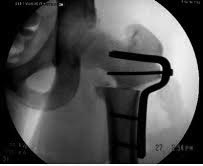

Здесь вариант установки 95 градусной пластины при варусной остеотомии.

Имя     : Varus osteotomy.jpg

Тип     : image/jpeg

Размер  : 25515 байтов

Описание: отсутствует

Url     : http://weborto.net:8080/pipermail/ortho/attachments/20150306/9569d1c1/attachment-0003.jpg